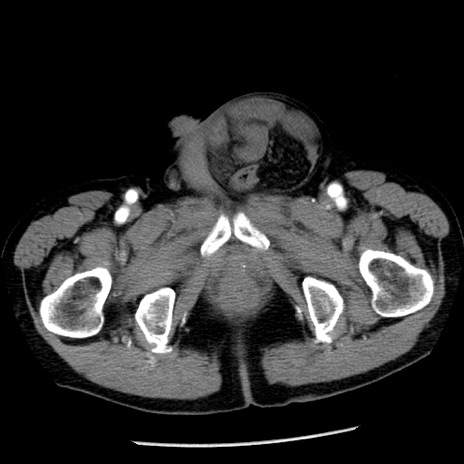

症例26(横断像)

【症例】80歳代男性

【主訴】嘔吐

【現病歴】昨晩2回嘔吐あり、今朝になっても嘔吐あり。来院。

【既往歴】胃潰瘍

【身体所見】意識清明、BT 37.6℃、BP 166/95mmHg、HR 100bpm、SpO2 97%、腹部:平坦・軟、腸蠕動音聴取良好、圧痛なし。

【データ】WBC 21900、CRP 1.46